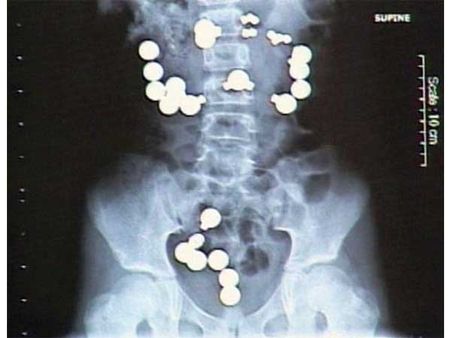

52 કેપ્સ્યુલ

એક નાઇઝિરીયન માણસને મલેશિયાના એરપોર્ટ પરથી જ્યારે પકડવામાં આવ્યો ત્યારે તેના પેટમાંથી 52 ડ્રગ્સની કેપ્સ્યુલ મળી. જે ખરેખરમાં જ મોટી માત્રામાં હતી.